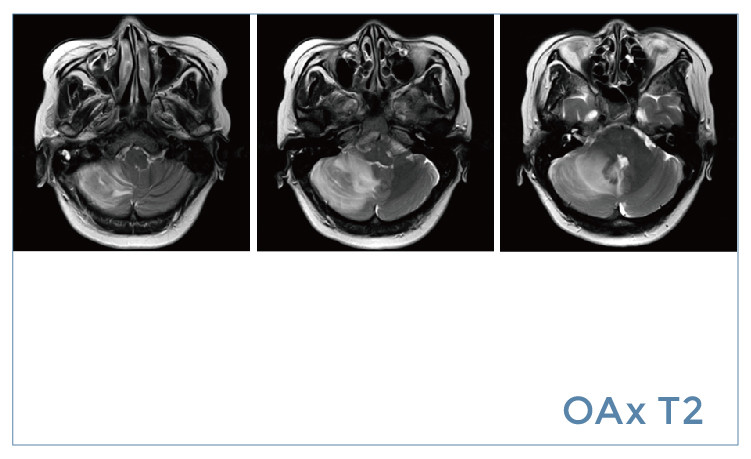

【朗润影像档案】磁共振影像病例分享(编号20190802)